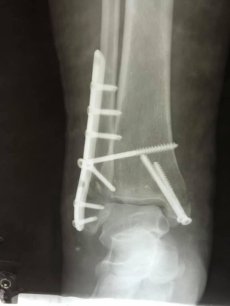

Пацієнтці виконали відкриту репозицію уламків з внутрішньою фіксацією. Операція пройшла успішно.